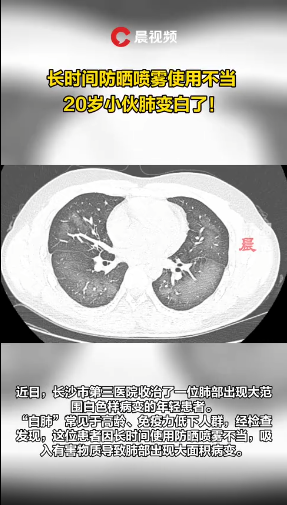

#一小伙对脸喷洒

防晒喷雾后检查出“白肺”#

近几年,因为不少明星爱用而大火的“网红产品”——喷雾式防晒霜,我们不推荐给儿童使用。

美国消费者权益组织曾发布“消费者报告”,警告喷雾式防晒霜可能存在健康风险,应避免给儿童使用。防晒霜中含有的化学物质容易通过口腔、鼻腔进入直接与气道黏膜产生反应不良影响。